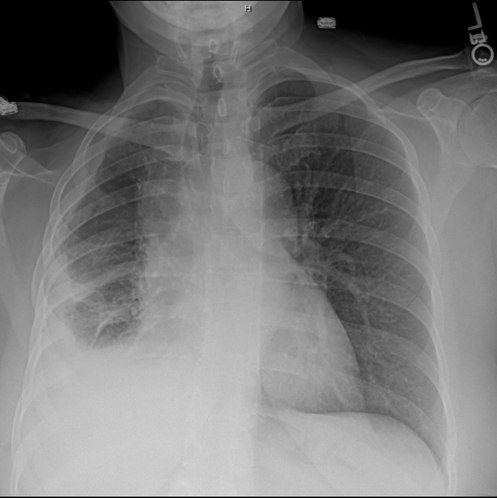

The tumor and concurrent pleural effusion may reduce lung function by restricting or preventing lung.

The classic description of malignant pleural mesothelioma is a thickening in the pleural space with encasement of the lung by a rindlike visceral pleura. Malignant mesothelioma is a rare malignancy. Malignant mesothelioma is a cancer caused by asbestos fibers. Treatment strategies for mesothelioma often include a combination of. Considerable progress has been made in.